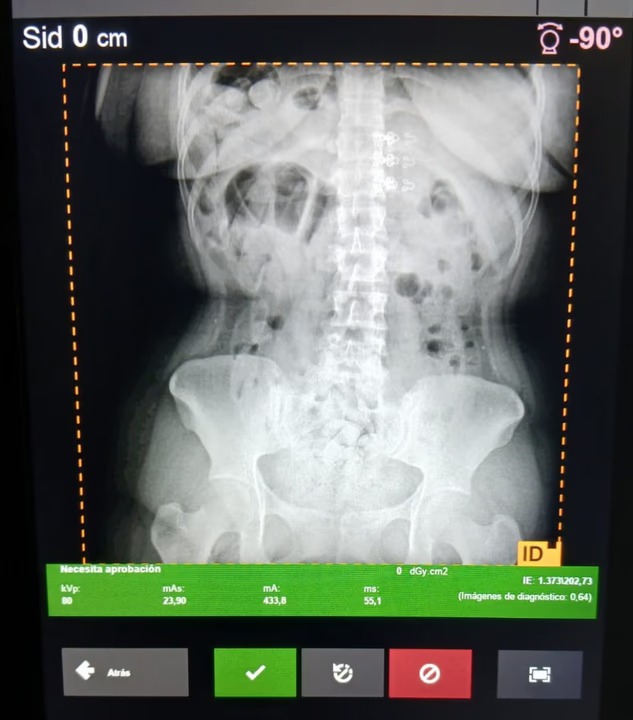

Durante la inspección, los funcionarios advirtieron que tres pasajeras presentaban molestias abdominales. Ante la sospecha de un hecho ilícito y priorizando el riesgo para la salud, los gendarmes dispusieron el traslado de las mujeres al Hospital de Trancas, donde las placas radiográficas revelaron la presencia de cuerpos extraños compatibles con cápsulas ingeridas.

Debido a la gravedad del cuadro, las ciudadanas fueron derivadas al Hospital Centro de Salud, en San Miguel de Tucumán, donde se procedió a la evacuación de un total de 198 cápsulas. Los envoltorios incautados fueron sometidos a la prueba de campo Narcotest, la cual arrojó resultado positivo para cocaína, con un peso total de 2 kilos con 328 gramos.